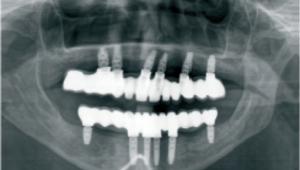

a. Situación clínica inicial del paciente con compromiso periodontal avanzado y movilidad severa de las piezas dentales. Evaluación radiológica previa al tratamiento para el análisis del volumen óseo y la planificación de implantes.

c. Situación clínica tras la fase quirúrgica del tratamiento, con colocación de implantes y prótesis provisional.